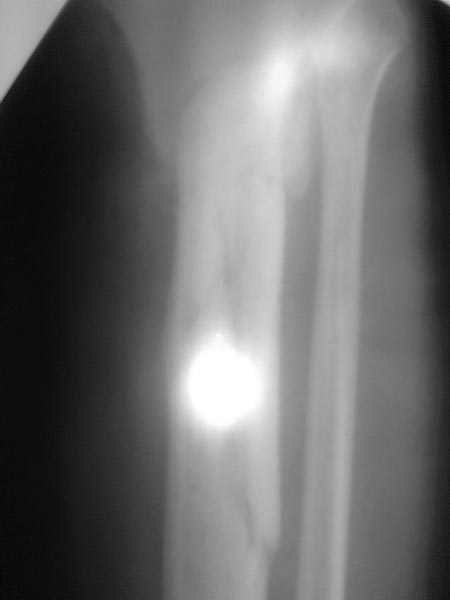

Все таки решились на штифт с антибиотическим покрытием. Выставляю R, в целом считаю неплохо вроде получилось.

Также через 5-7 дней удалили винт который не попал в штифт под м/а( раньше не получилось-в связи с организационными моментами.

Швы сняли ок.16 дней после операции- с первичным заживлением, отек незначительный - при выписке на голени.Сосудистых и неврологических нарушений при выписке нет.

При выписке рекомендован прием прадаксы 150 мг 1р/д до 20 дней. Нагружать конечность не разрешили до удаления дистального винта блокиратора до 6 нед. с момента операции.